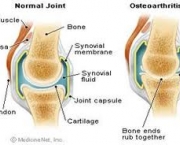

O desenvolvimento dessa doença se dá pelo desgaste das cartilagens responsáveis por revestir as extremidades ósseas de forma a causar muita dor e até mesmo deformações. A incidência de Artrose no Joelho é bastante comum porque as articulações do joelho estão dentre as articulações mais afetadas pela sobrecarga de peso.

O principal sintoma que a Artrose no Joelho apresenta é a dor constante, essa dor tende a piorar quando é feito um grande esforço ou mesmo com a rigidez matinal das articulações comprometidas. O indivíduo pode ter alguma dificuldade em apoiar o seu peso no joelho que sofre com o problema.

Outro sintoma bastante significativo desse problema nos joelhos é sentir um tipo de crepitação quando faz algum movimento com os joelhos. Devido ao crescimento de ossos ao redor do joelho o indivíduo sente que o joelho está inchado. Quando uma pessoa começa a sentir além de dores nos joelhos perda de sua função (de aguentar carga) deve procurar por um especialista.